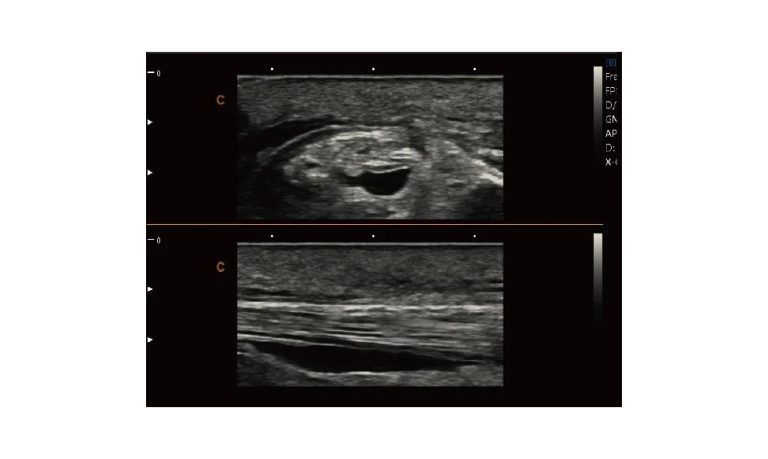

Ultrasound

Wide range of Ultrasound machines that suites a variety of applications from abdominal to rectal scans, we take in consideration how the world is moving towards mobility and mobile applications.

SonoScape Pro Pet E11

Smart Imaging

Introducing the first portable ultrasound with the C-Field+TM platform, redefining diagnostic imaging. Designed for veterinarians, it delivers unmatched clarity, ultra-fast processing, and seamless adaptability for all species. Experience Smart Imaging, Heartfelt Care—anywhere.

Equipped with cutting-edge veterinary software and optimized workflows, it embodies our commitment to Smart Imaging, Heartfelt Care – Wherever Their Journey Leads, with unparalleled performance and adaptability, this innovative system empowers veterinarians to provide exceptional care across all diagnostic applications,

Esaote MyLab Sigma; So Fast, So Easy

Esaote’s new MyLab™SigmaVET is the smart, portable solution that allows use of an ultrasound whenever a quick and complete diagnosis is required.

EBIT50/60 VET

All the power you need

The EBit provides all the power you need for today´s challenging clinical environment, yet remain ultra-portable, ultra-affordable. With its cutting-edge imaging technologies, precise and intuitive workflow, ergonomic and eco-friendly design, versatile transducers for all applications from top to toe, we firmly believe the EBit to be the very best portable ultrasound in its class today.

ECO5 VET

Ultra-Portable, Ultra- Affordable, Color doppler

The multi-purpose user presets, comprehensive measurement & report system, built-in EasyView image achieve system, quick image storage / retrieve / transfer, one-button direct print, make the complete workflow better than what you can dream of.